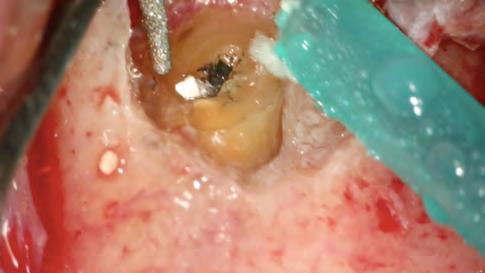

Se inició la terapia endodóntica del diente 21. Después del acceso, el conducto fue irrigado con Hipoclorito de Sodio al 5%, seguido de EDTA al 17%, ambos con PUI y Easy clean. A través del uso del microscopio operatorio, fue posible visualizar la extensión de la cavidad reabsortiva (Figura 5). Durante la preparación químico-mecánica hicimos una irrigación abundante con sustancias químicas auxiliares con capacidad solvente orgánica efectiva y punta de ultrasonido esférica para remover y diluir el tejido pulpar remanente.

Figura 5 - Cavidad reabsortiva